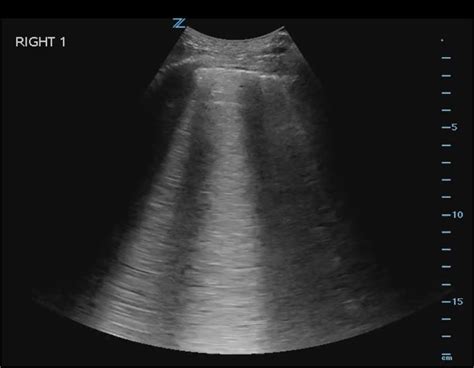

To accurately assess for B Lines Ultrasound artifacts, clinicians should utilize a high-frequency linear probe for better resolution of the pleural line, or a curvilinear probe for deeper penetration. The patient should be evaluated in the supine or semi-upright position, scanning across multiple zones of the thorax.

1. Place the probe perpendicular to the ribs in an intercostal space.

2. Identify the pleural line—the hyperechoic line moving between the two ribs.

3. Observe the movement of the pleura (lung sliding) to ensure proper positioning.